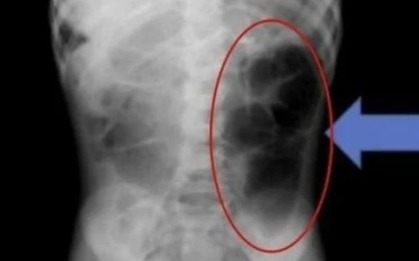

Em được gia đình đưa đến bệnh viện vì đau bụng, tiêu chảy kéo dài và sụt cân nhanh. Kết quả kiểm tra cho thấy, em đã mắc ung thư đại tràng giai đoạn cuối, thậm chí bệnh đã di căn nhiều nơi trong ổ bụng.